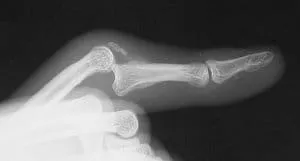

imgi 16 PIP fracturedislocation

Volar plate injuries

A dislocated finger is often just ‘popped’ back in, buddy strapped to...